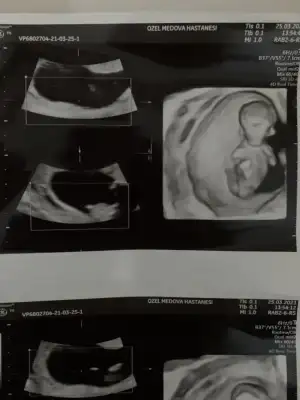

benım gebelıgımın cınsıyetını dogru tahmın etmıstın canım😍bu da kardesımın 11+6 goruntusu

Eklentiler

• A44982B2-0C3B-42AC-BFF0-F71F4BE3B402.webp

A44982B2-0C3B-42AC-BFF0-F71F4BE3B402.webp

7,9 KB · Görüntüleme: 100

• 7144264D-2964-47AE-88BB-CDC19ECA621F.webp

7144264D-2964-47AE-88BB-CDC19ECA621F.webp

6,6 KB · Görüntüleme: 103